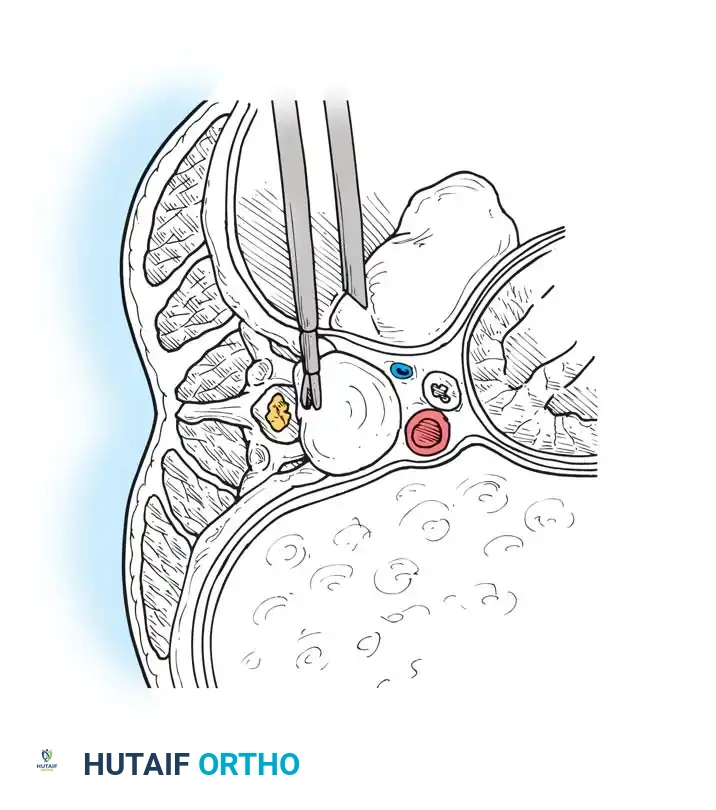

1. Vascular Mobilization: The segmental vessels overlying the target vertebral bodies are carefully ligated and divided to allow mobilization of the great vessels.

2. Rib Head Resection: The rib head articulating with the target disc space is resected. This is a critical step to allow direct observation of the pedicle and the neural foramen caudal to the disc space.

Image

1. Pedicle Removal: The cephalad portion of the pedicle is removed using a high-speed burr and Kerrison rongeurs. This exposes the poster